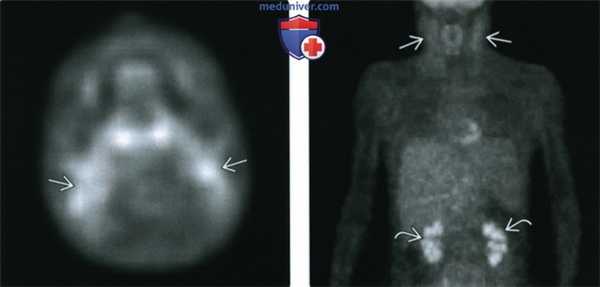

(Слева) КТ с КУ, аксиальная проекция, девушка с крупным, активно накапливающим контраст лимфоузлом уровня IIB слева. Обратите внимание на выраженную сосудистую сеть. У пациентки был обнаружен гиалиново-васкулярный тип унифокальной болезни Кастлемана.

(Справа) КТ с КУ, парасагиттальная проекция. Диффузное увеличение лимфатических узлов, окружающих грудино-ключично-сосцевидную мышцу. В отличие от предыдущих случаев, активного накопления контраста нет. Пациент страдает плазмоцитарным типом болезни Кастлемана, мультицентрическая форма.